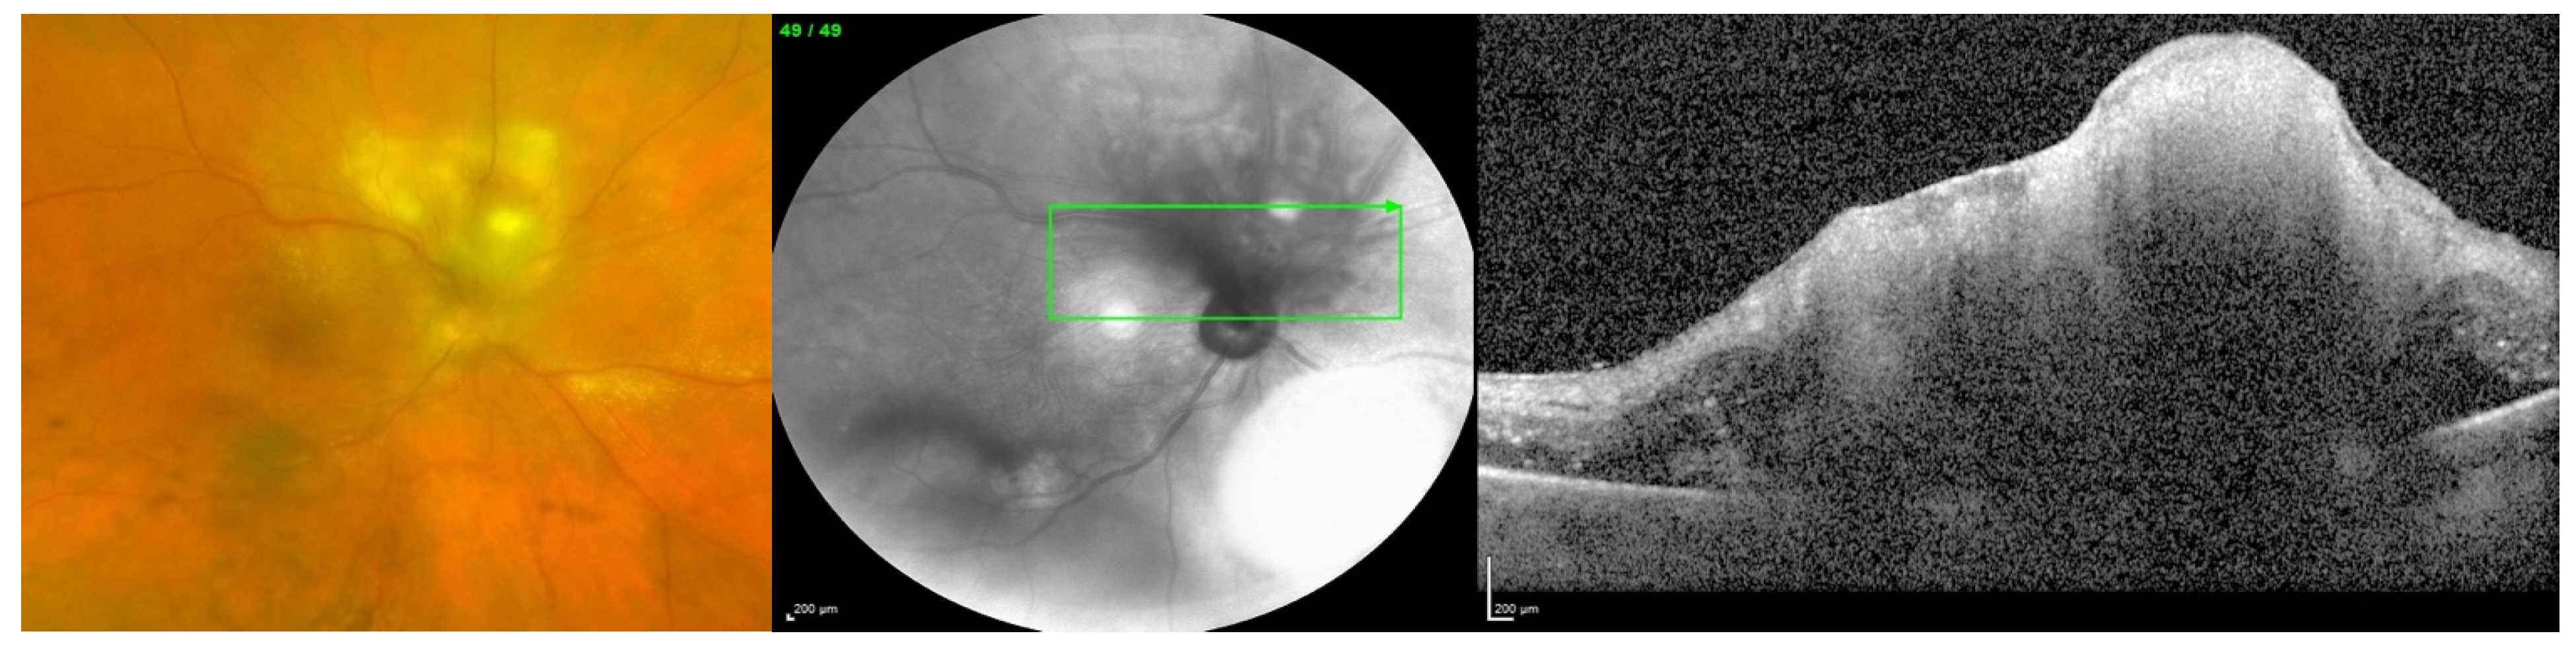

Endogenous endophthalmitis refers to the hematogenous dissemination of organisms causing intraocular infection. Endogenous endophthalmitis is less common, should be considered in the setting of fungemia, and is associated with specific risk factors [1]. Systemic immunosuppression without fungal bloodstream penetration is not considered a definitive risk factor; rather, the risk is in the combination of both. Examples of factors that can lead to penetration of the bloodstream by fungi include long-term indwelling intravenous catheters, prolonged hospital stays, abdominal surgery, and intravenous drug use. [4,5]. Figure 1 shows a case of endogenous fungal endophthalmitis, which was identified and correlated with a history of intravenous substance abuse, one of the definitive risk factors. Figure 2 also displays a case of endogenous fungal endophthalmitis, with a lesion characteristic of typical infection. When it comes to identifying the specific fungal species responsible for endogenous fungal endophthalmitis, the most frequently encountered organisms include Candida albicans and Aspergillus [6,7]. Other causative microorganisms include C. dulineniesis, C. tropicalis, and A. niger [6,7]. However, the precise proportions can vary depending on the data reported in the literature. In a study involving 27 cases of endogenous endophthalmitis, Binder et al. observed that among their 14 patients with fungal infections, 10 had Candida albicans infections (accounting for 71.4%), while 4 had A. fumigatus infections (28.6%) [8]. In contrast, Mir et al. examined a much larger sample of 56,839 cases of endogenous endophthalmitis and found that Candida infections were present in 6.7% of cases, while Aspergillus infections occurred in 0.4% of cases [5]. Additionally, in a study of 57 cases of endogenous endophthalmitis conducted by Lim et al., they identified C. albicans as the most common fungal cause, occurring in 9 cases (15.8%) [9]. Taken together, these findings suggest that yeasts, particularly Candida species, appear to be more commonly associated with endogenous fungal endophthalmitis, while molds, particularly Aspergillus and fusarium, are more frequently implicated in exogenous fungal endophthalmitis. However, it is important to note that a direct comparison or conclusive statement on this matter has not been formally studied or established.

Figure 1. Endogenous fungal endophthalmitis in a patient with a history of IV substance use. Color fundus photo (left) showing vitreous haze and a retinal lesion with surrounding retinal edema and exudates. Near-infrared image (middle) and optical coherence tomography (right) of the same eye showing an irregular lesion of the retina and the underlying choroid.